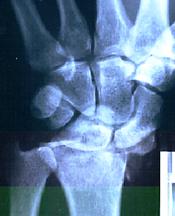

The result is shown in the x-ray below: over an inch of the bone shattered. (Oops!)

I asked the emergency doctor when he got initial x-rays if it was broken and he said “No. It’s shattered”

He said “Imagine you have a wine class and you break the stem. That is a break, Drop the bowl of the glass onto a tile floor and it shatters. That’s what you have done to your wrist!”

The surgeons said that the break was not fixable. They would have just fused the bones together, and locked the wrist, but there was nothing to join.

They opened the wrist, took out the bones replaced the largest pieces with half a dozen pins then used the left over bones to fill in the cracks in a sort of bone graft.

They said that when there are more than three points of break that the circulation is compromised and the coating on the bone dies, the bone does not heal, and you have bone on bone in the joint and a lot of pain.

They said that in six weeks when the bone had set I would be begging them to fuse the wrist so there was no movement and no pain.

By that time I was working with nutrition products and the doctors allowed me to ‘self-medicate’ with nutrition while in hospital. If you are interested in what I used drop me a line, Basically it involved high use of Omega 3’s, antioxidants, calcium and a few other things. ( I also had 4 churches and about 20 individuals praying for me)

Six weeks later I want back to the surgeons, taking x-rays from my local hospital. They reviewed them, check the movement I had, and the apparent lack of pain, and sent to their own people for another set of x-rays.

They then said that they could not explain it but that there was no point where the circulation had not returned to the bone and that it appeared to working normally. They took out the pins and I walked out. I have never had trouble with it since.

Now, a couple of decades later, for the past five years my sport of choice has been in the gym doing power lifting with the young ones. I lift pretty heavy weights now and the wrist still does not give me any trouble.